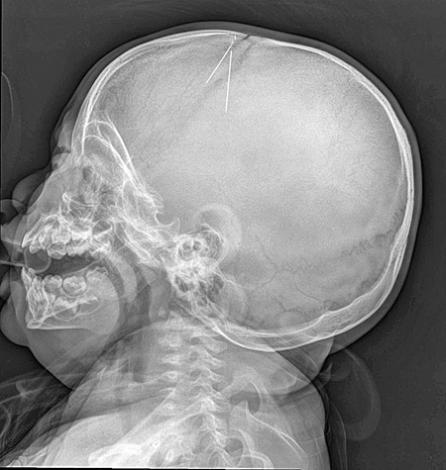

穿过大静脉 可引发癫痫

案情透露,男婴上月底从楼上摔下后不断哀嚎,其母发觉有异状,仔细检查后发现儿子头顶上有3个流血的小孔,经拍X光检查,赫然发现男婴天灵盖插有3根约5公分的小针,研判应是缝衣针。医生表示,针的位置是在比较危险的地区,穿过脑正中央的一条大静脉,“久一点或男婴碰撞,都可能致命”,也可能引发癫痫。

医生指出,由于男婴插针的部位几乎已愈合,看不到伤痕,研判插入已有一段时间,由于插入位置由头心往下,危及脑部,动刀十分危险,加上男婴年纪太小,手术风险很高。最后转往台大医院,前天做手术取出3根针,院方认为事态严重,特地将3根针列为“凶器”证物,送交警方侦办。